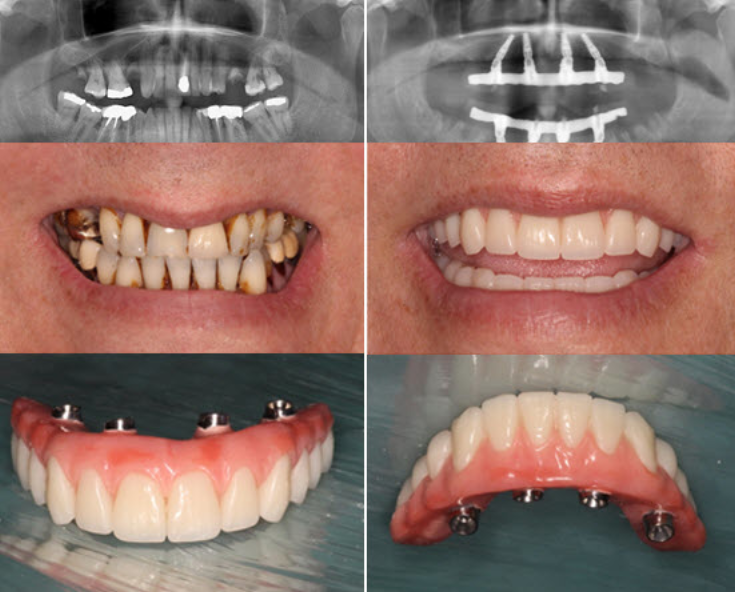

Restauración total de la sonrisa y función masticatoria en paciente con pérdida severa de hueso y dientes.